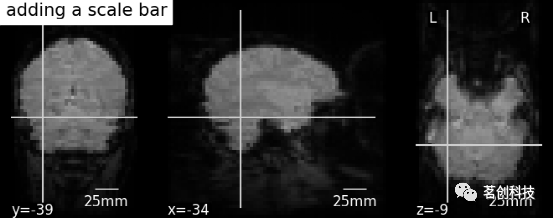

# 进一步的设置可以通过scale_*关键字参数来实现。例如,将单位更改为mm,或者使用不同的比列尺大小

display = plotting.plot_anat(mean_haxby_img,

title="adding a scale bar",

cut_coords=[-34, -39, -9])

display.annotate(scalebar=True, scale_size=25, scale_units='mm')